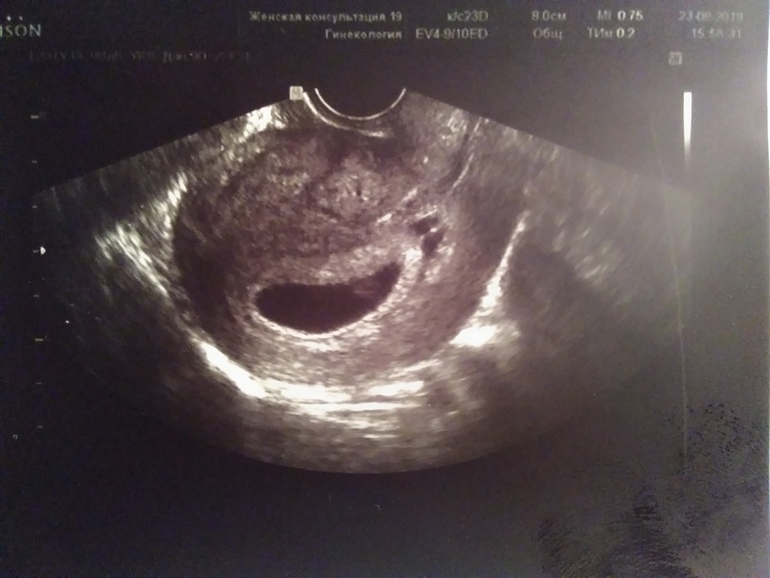

У нас тоже была отслойка во вторую беременность - именно красная кровь была на 9й неделе, немного. Да, как девочки пишут, выписывали транексам. Но ни в коем случае нельзя пить без назначения врача, тем более Вы на клексане, а транексам наоборот сгущает кровь. Тут только гинеколог скажет, что делать. Тонус на узи выглядит так:

вот так выглядит тонус по задней стенке!

Тоже было. Прописали Дюфастон сразу 3 таблетки выпить и потом три раза в день, Транексам от кровянистых выделений и Утрожестан вагинально на ночь. Лежала 5 дней дома, ничего не делала, только лежала. Отслойка за это время прошла. Выглядит она на УЗИ как темное пятнышко возле плодного пузыря.

А где задняя стенка и как он проявляется на картинке? Простите за вопросы. Хочу разобраться